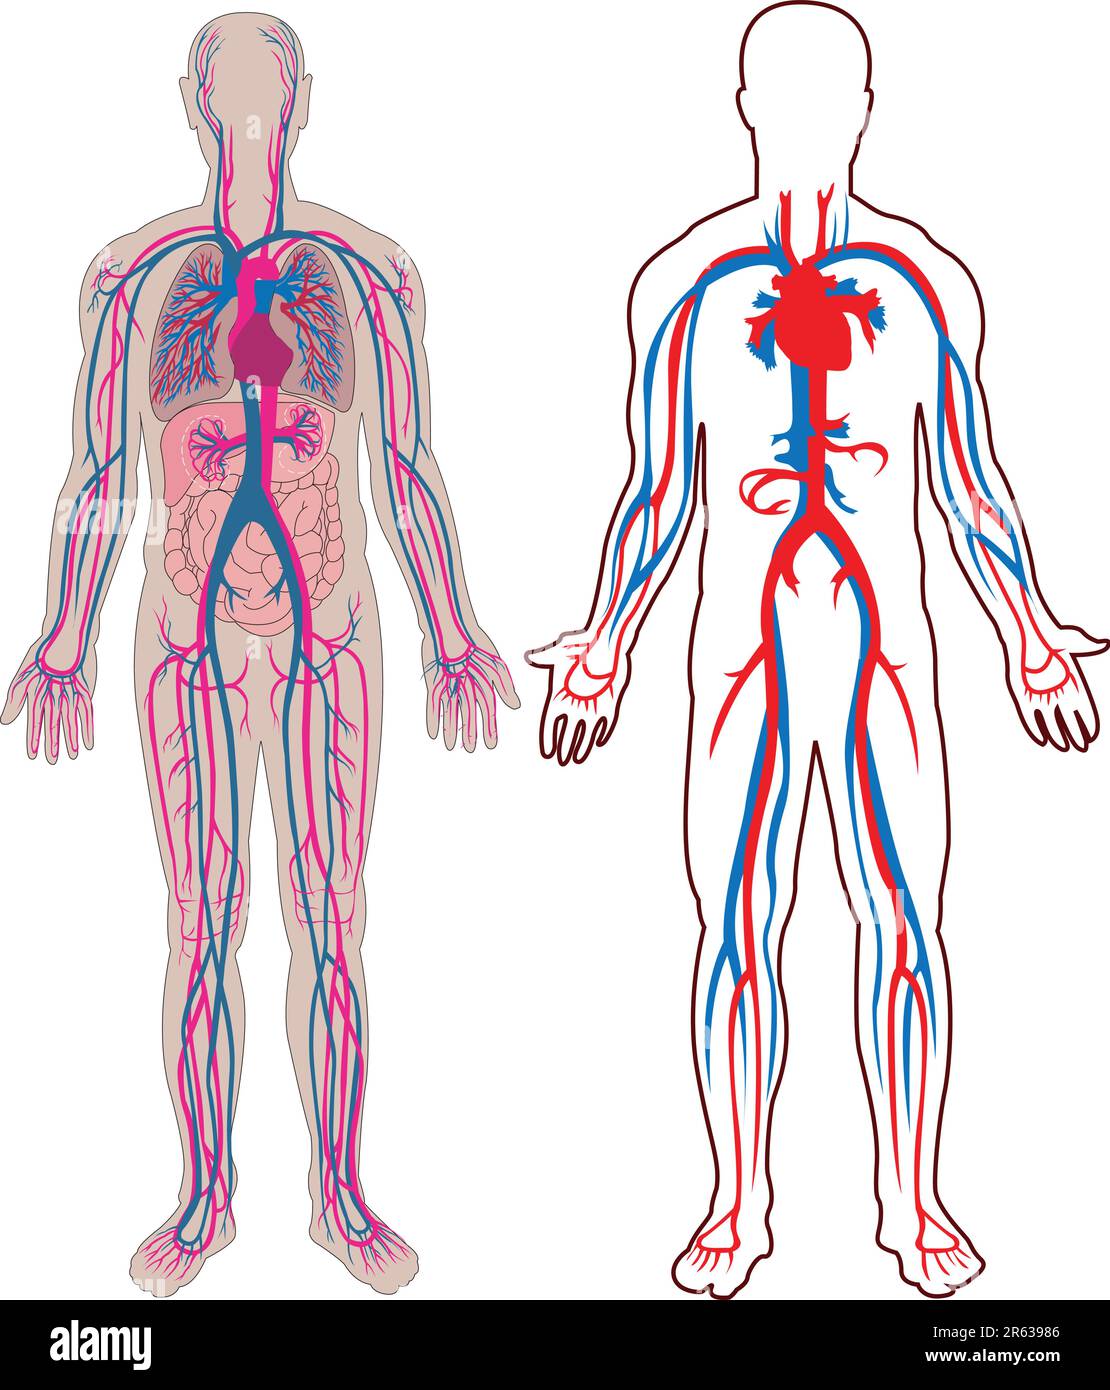

Diagram of the human vein and anatomy in vector Stock Vectorhttps://www.alamy.com/image-license-details/?v=1https://www.alamy.com/diagram-of-the-human-vein-and-anatomy-in-vector-image554492854.html

Diagram of the human vein and anatomy in vector Stock Vectorhttps://www.alamy.com/image-license-details/?v=1https://www.alamy.com/diagram-of-the-human-vein-and-anatomy-in-vector-image554492854.htmlRF2R63986–Diagram of the human vein and anatomy in vector